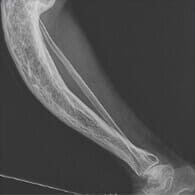

A könyököm már két éve rettenetesen fájt, és nem volt időm szakemberhez menni. Eleinte a közeli gyógyszertárból származó kenőccsel tudtam csillapítani a fájdalmat, és valahogy úgy tűnt, hogy egyre könnyebb lesz. De aztán hirtelen egy dudor keletkezett a könyökömön, mintha bursitis lenne. Nagyon megijedtem. Köszönet a feleségemnek, aki ragaszkodott hozzá, hogy megrendeljem ezt a terméket, és megkaptam a Remofixt. Néhány nap múlva a duzzanat eltűnt, a fájdalom pedig teljesen megszűnt. Végre jól érzem magam.